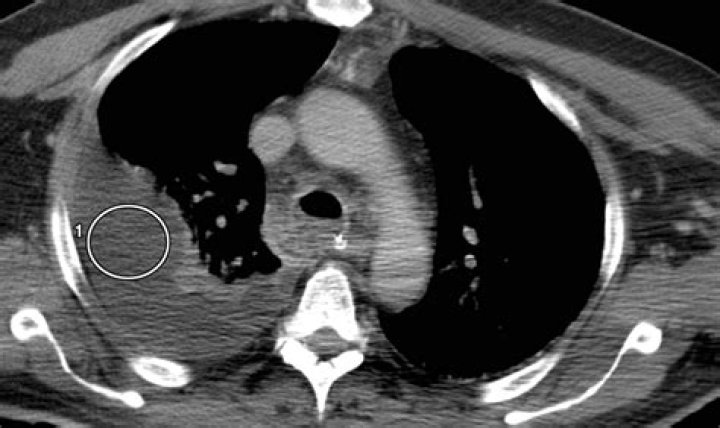

What is chylothorax? Chylothorax is a rare condition in which lymphatic fluid leaks into the space between the lung and chest wall. When this fluid builds up in the lungs, it can cause a severe cough, chest pain and difficulty breathing. Chylothorax is a lymphatic flow disorder.

Thoracentesis and pleural fluid analysis are the criterion standards to establish a diagnosis of chylothorax. Alternatively, in a postsurgical patient, tube thoracostomy output can be analyzed. Pleural fluid analysis for triglyceride content helps to confirm the diagnosis of chylothorax.

Chylothorax is a rare condition that results from thoracic duct damage with chyle leakage from the lymphatic system into the pleural space, usually on the right side. It has multiple aetiologies and is usually discovered after it manifests itself as a pleural effusion.

Chylothorax is characterised by the accumulation of chyle, a lipid and protein rich fluid within the pleural space. It often occurs due to thoracic duct trauma which can be caused by increased pressures. On Koala, this postoperative complication is often seen post cardiac surgery in patients with redivac drains insitu.